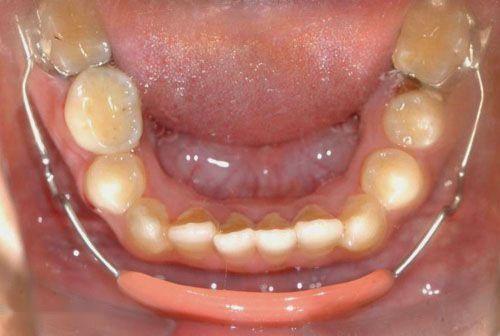

2. 后牙反合

后牙反合表现为下后牙咬在上颌后牙的外侧、上牙弓狭窄。单侧后牙反合患者会出现不同程度的颜面不对称,当上牙弓进一步狭窄时,会形成双侧后牙反合,影响其咀嚼。

矫治方法:后牙反合的患儿往往因为有龋齿而形成偏侧咀嚼的习惯,应及时治疗后牙区龋齿,纠正其偏侧咀嚼的习惯。乳牙列和混合牙列期的主要治疗方法主要通过调合以及扩展上牙弓宽度。常用的矫治器为Haas扩弓器和Hyrax扩弓器。